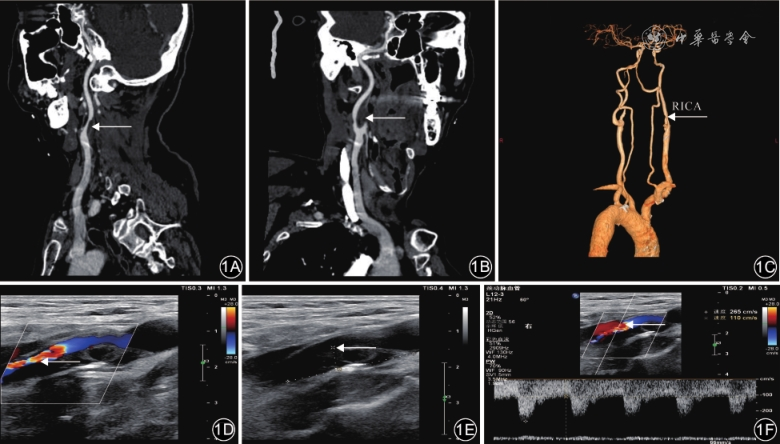

以DSA检测结果为金标准,除了颈部血管超声诊断颈动脉轻度狭窄的灵敏度较低、能谱CT诊断颈动脉轻度狭窄的阳性预测值较低外,能谱CT及颈部血管超声诊断不同程度颈动脉狭窄均具有较高的准确率、灵敏度、特异度、阳性预测值及阴性预测值,见表2。典型病例见图1。

DSA在双侧颈总动脉上共检出易损斑块1 672个。颈部血管超声在双侧颈总动脉上检出易损斑块876个,检出率为52.39%(876/1 672),其中软斑块384个、表面不规则斑块80个、溃疡斑412个,能谱CT在双侧颈总动脉上检出易损斑块367个,检出率为21.95%(367/1 672),均为软斑块。血管超声易损斑块检出率高于能谱CT,差异有统计学意义(P<0.001)。见表3。